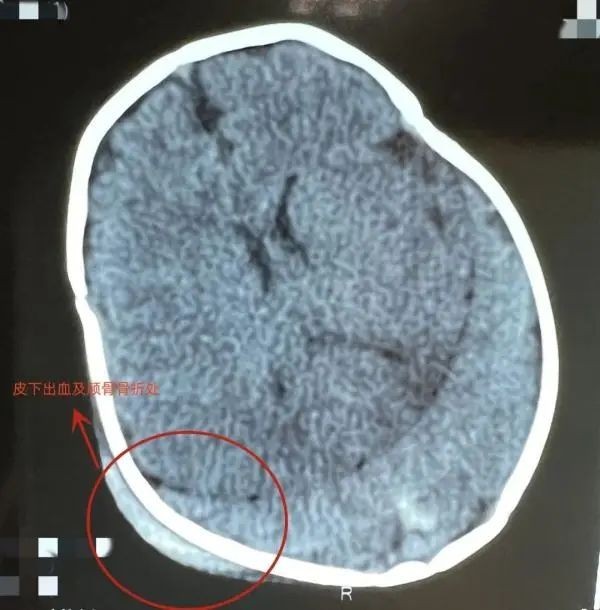

据医院小儿外科主治医师顾春晖介绍,家长抱着孩子坐在副驾驶位,突然急刹车,孩子一头撞在了中控台上,头部肿胀、哭闹不止。经过头部CT检查,发现皮下有出血,颅骨有凹陷骨折,颅内也有少量出血伴有脑挫伤。经过治疗,孩子病情平稳,出血没有继续增加。